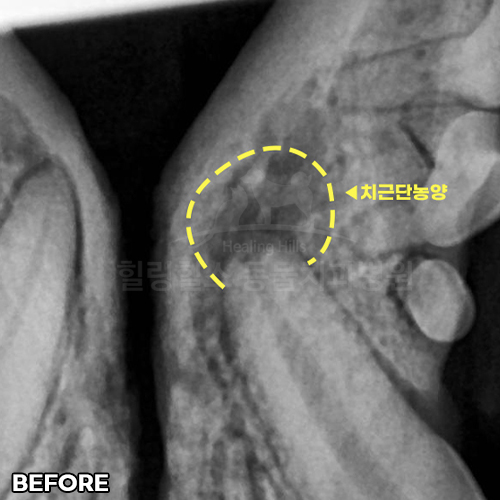

[신경치료 4개월 후 사라진 치근단농양!!]

샘플